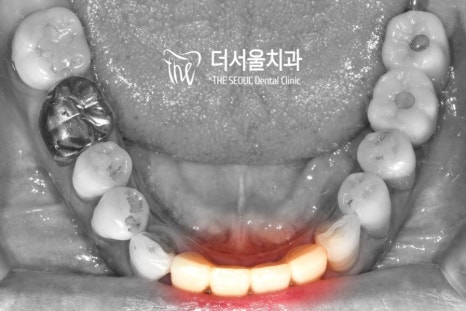

이전에는 잇몸이 내려앉고

안에 있는 조직이 드러나서

심미성이 떨어질 수 밖에 없었는데요.

실제 자연치와 유사한

지르코니아를 사용하여

좀 더 건강한 치아를 만들어주었습니다.

앞니임플란트 와 더불어 아래 쪽의 브릿지도

심미성은 물론이며 컨택, 교합이 잘 맞게끔

제작이 된 것이 관찰되네요.